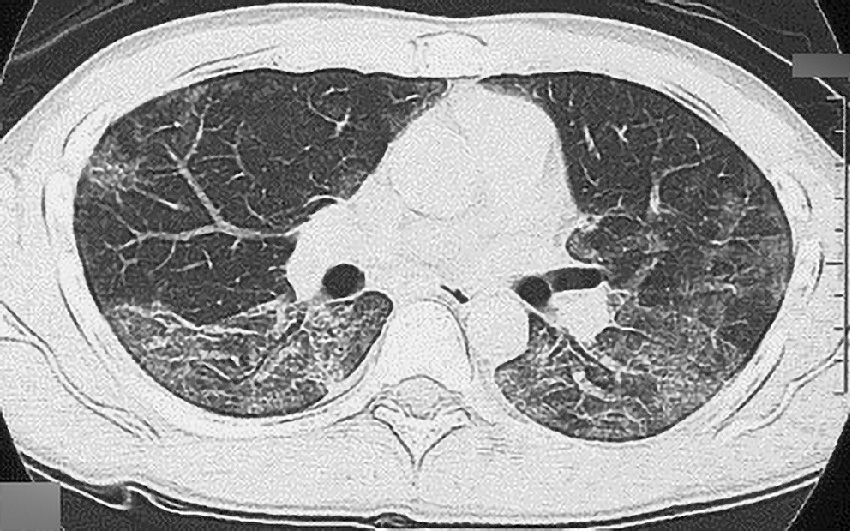

ⓔ図7-5-6 ニューモシスチス肺炎のCT所見 両肺びまん性にすりガラス様陰影がみられる.